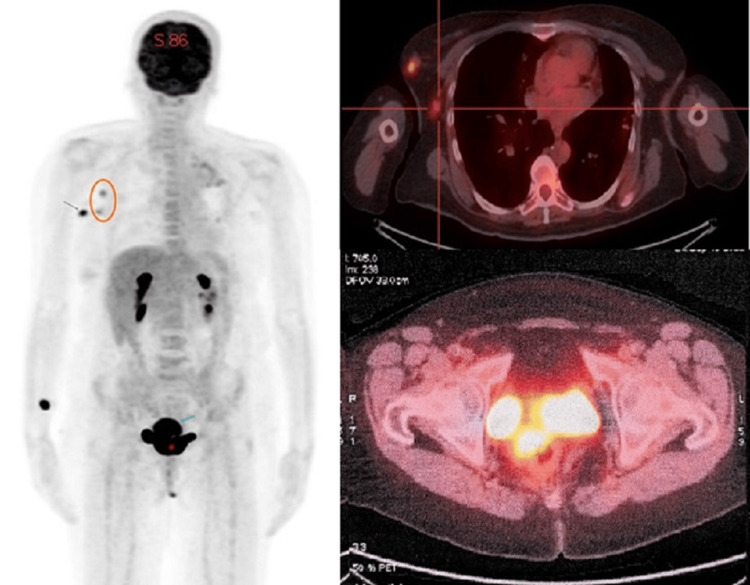

Subsequently, an 18F-FDG PET-CT scan was conducted for comprehensive staging and to evaluate for any additional malignancies. The PET-CT scan revealed significant hypermetabolic activity in both the cervix and the right breast, each characterized by high standardized uptake values (SUVs), strongly suggesting the presence of malignancies in both locations. Furthermore, the PET-CT scan showed the involvement of the right axillary lymph nodes, which also exhibited increased metabolic activity, consistent with the findings from the CT scan. Importantly, no distant lesions were detected (Figure 5).

Figure 5. The 18F-FDG PET/CT shows simultaneous hyperfixation of the breast nodule with ipsilateral axillary lymphadenopathy and the cervical mass, without evidence of suspicious distant lesions.